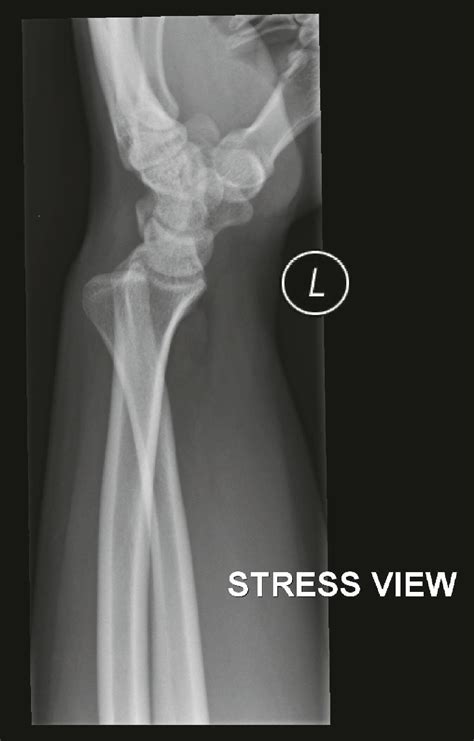

Diagnostic Procedures

If you suspect a stress fracture wrist, professional medical intervention is non-negotiable. Because hairline fractures are often too small to be seen on standard X-rays, doctors may require more sensitive imaging techniques. A physical examination will involve checking for point tenderness and assessing the range of motion.

| X-ray | Limited; often fails to show early hairline cracks. |